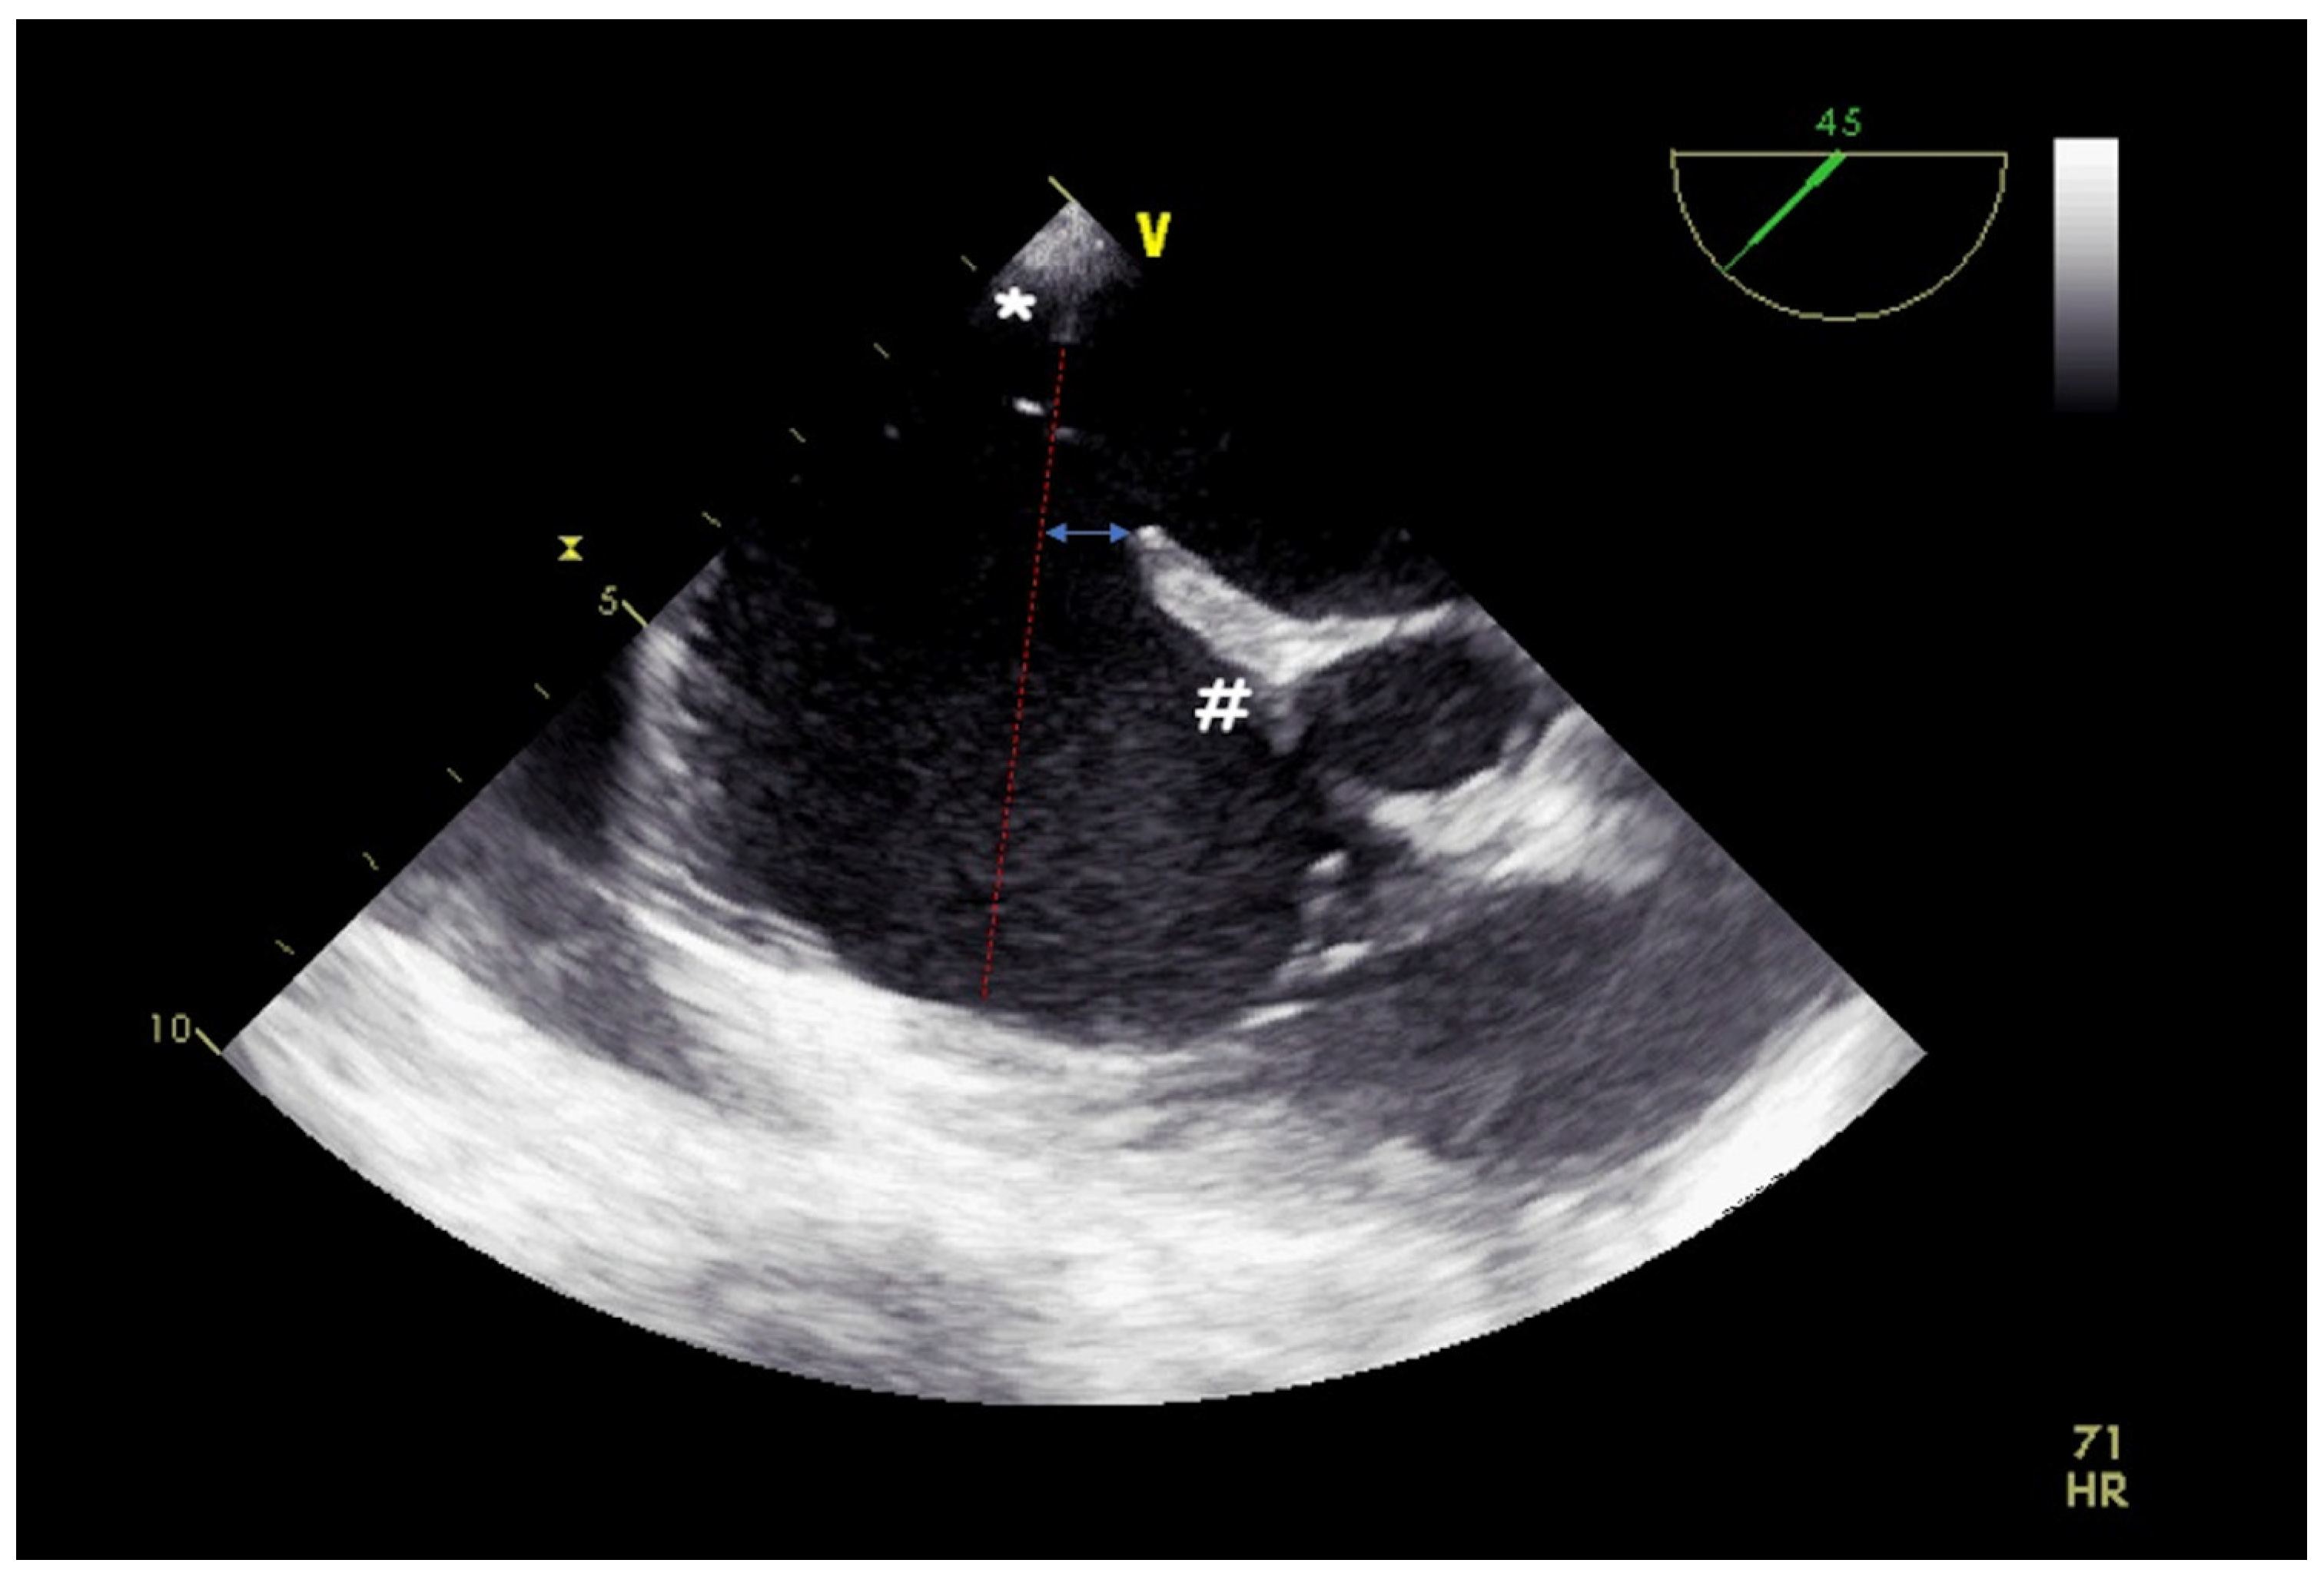

2. Atrial Septal Defect Closure

| Misaligned ASD | distance of separation between the septum primum surface and the septum secundum one (if present) |

| Double atrial septum | separation between the left atrial and right atrial rims of the defects (if present) |